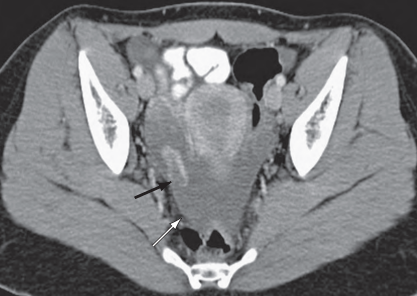

Corpus luteum 의 hemorrhagic cyst소견

검정 화살표 : 조영증강되는 황체낭종, 흰색 화살표 : 골반 내 fluid collection (hemoperitoneum)